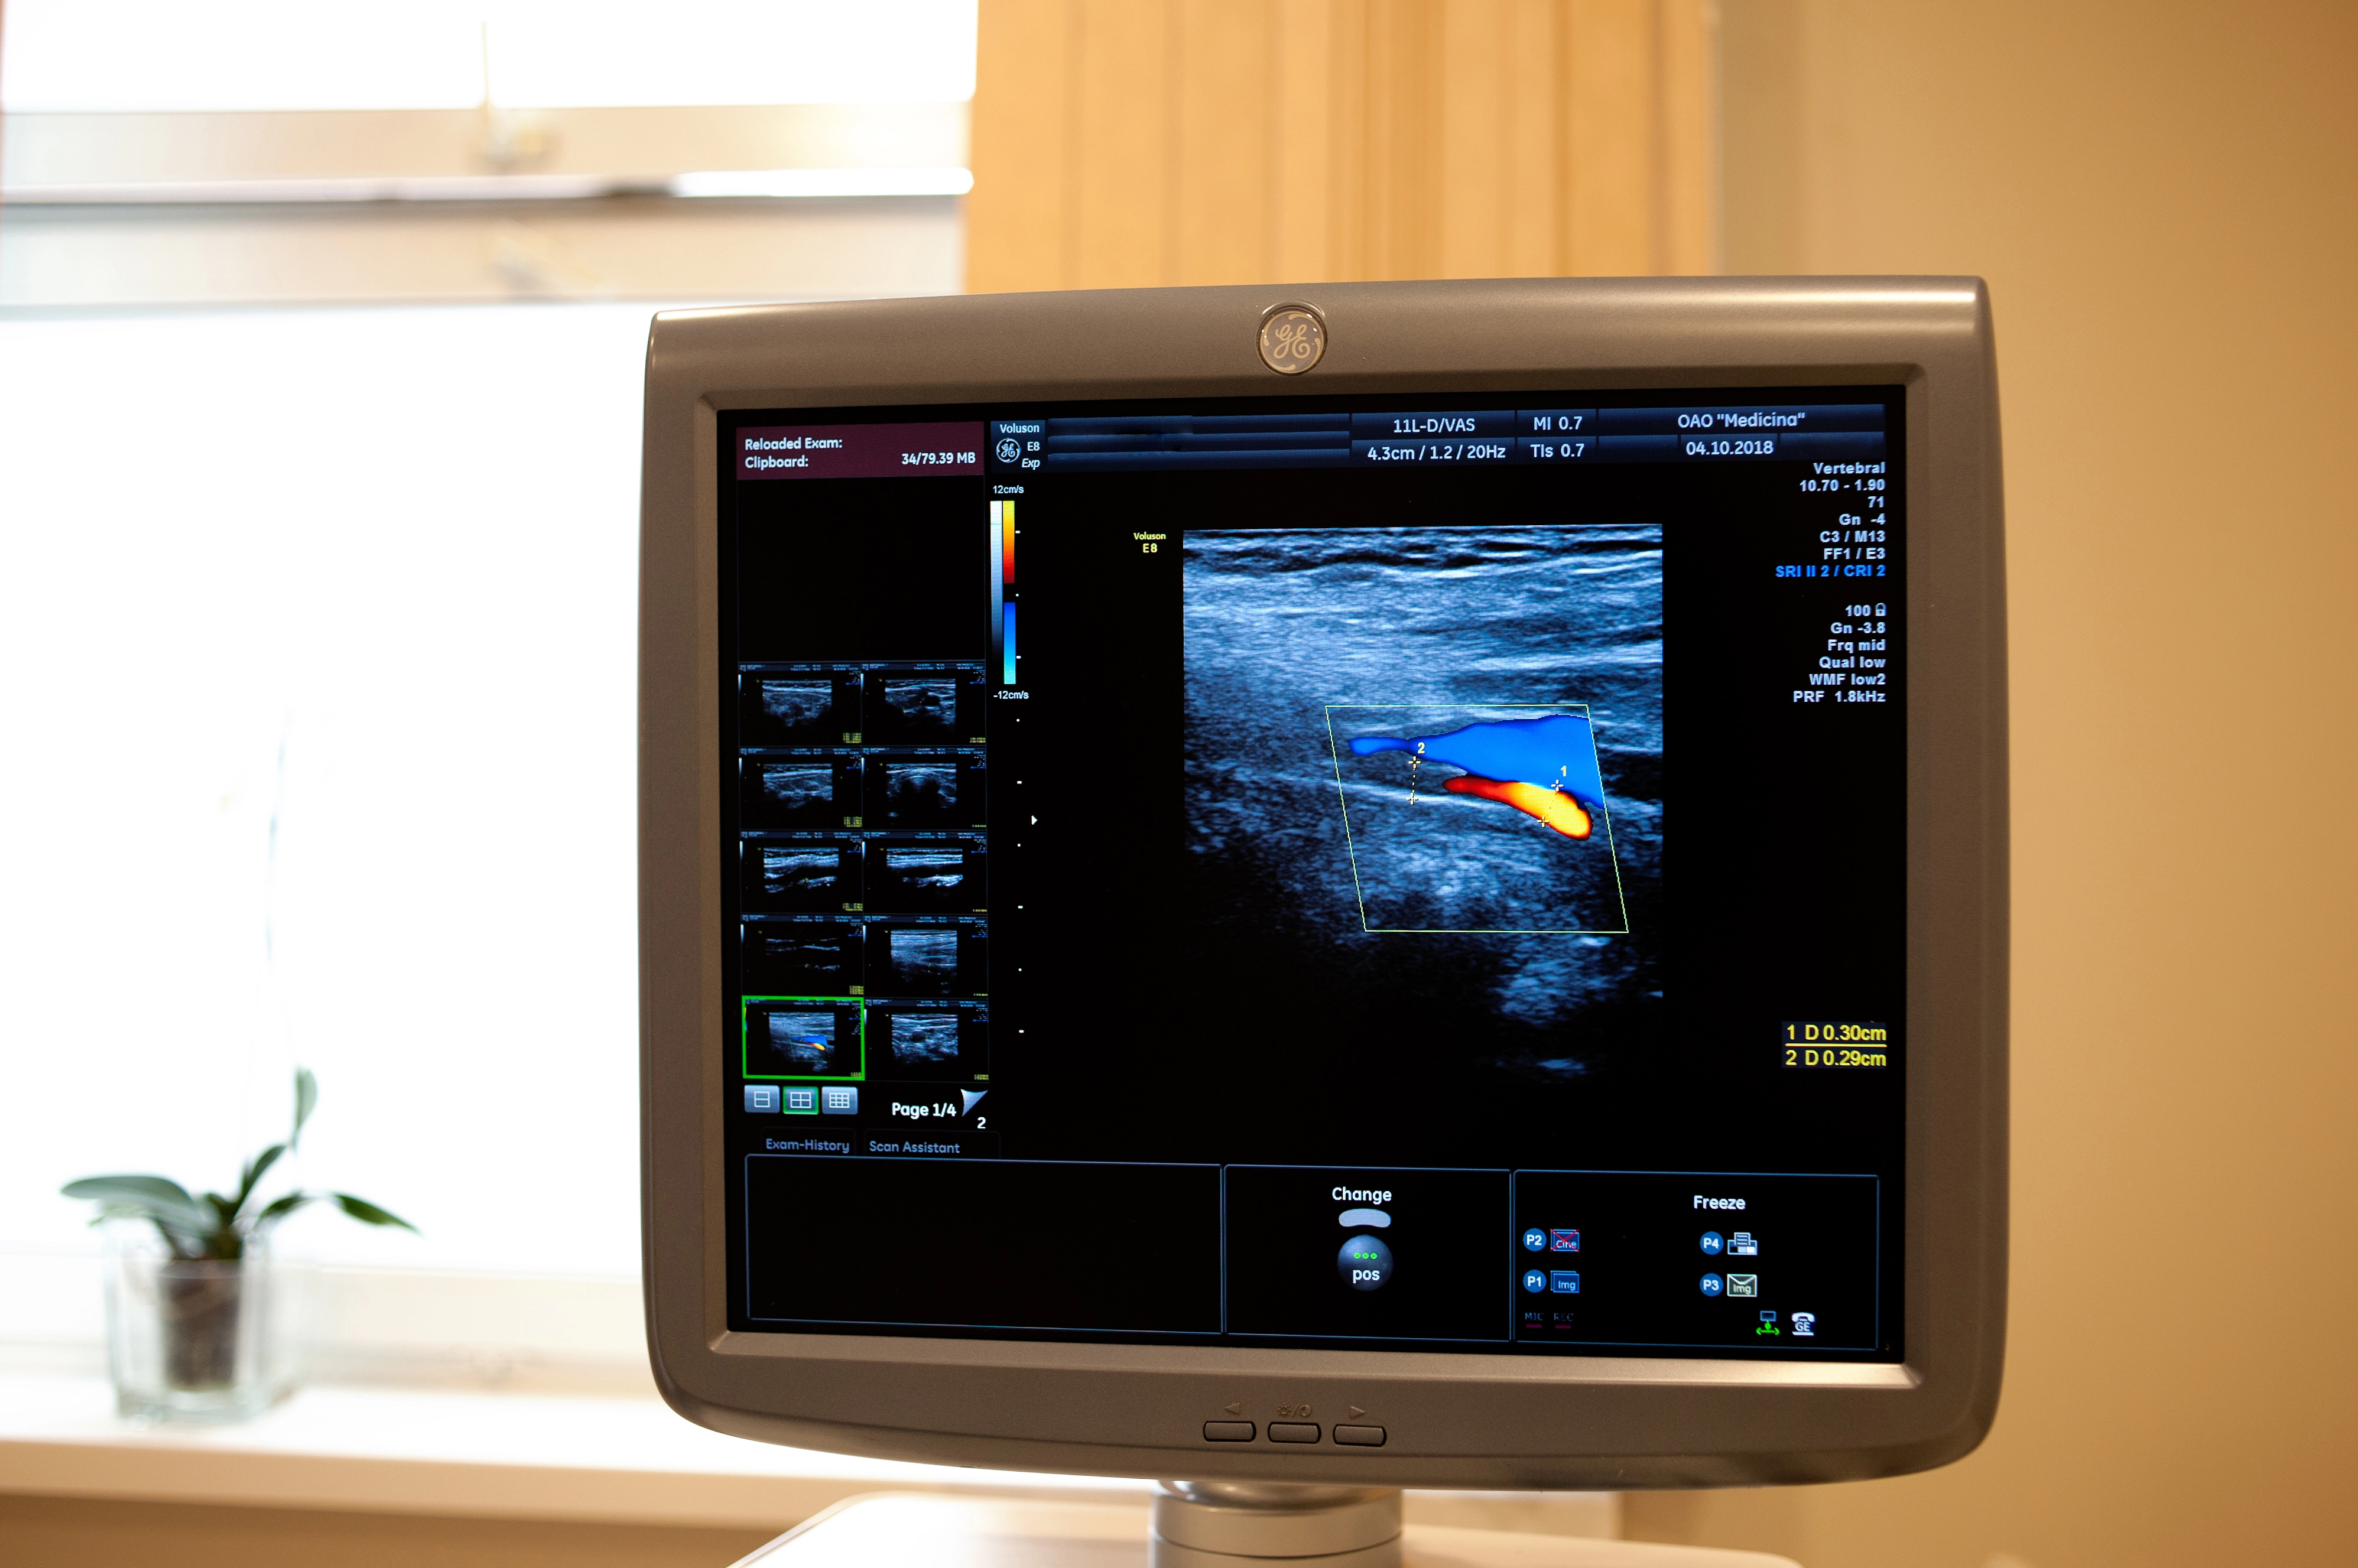

АО «Медицина» (клиника академика Ройтберга) предлагает сделать УЗИ сердца в Москве на инновационном оборудовании от ведущих медицинских брендов в удобное время. Высокая квалификация специалистов клиники, полный комплект диагностического оборудования, возможность проконсультироваться у специалистов других направлений и эффективность применяемых медицинских методик являются несомненными преимуществами обращения в один из ведущих медицинских центров Москвы – многопрофильную клинику АО «Медицина».

Проведение УЗИ в Москве

При обследовании в АО «Медицина» (клиника академика Ройтберга) в Москве пациентам необходимо снять верхнюю одежду и лечь на кушетку на левый бок, что позволит получить изображение в четырехмерной позиции. Врач проверяет пульс и давление, затем на тело пациента наносят специальный гель. На обследуемой области крепятся датчики. Обследование сердца продолжается 15-20 минут. Расшифровку данных пациент может получить сразу по окончании обследования.